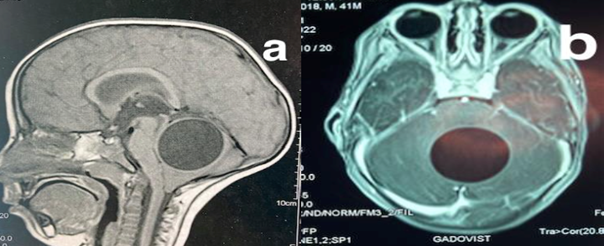

Brain computed tomography (CT) scan and magnetic resonance imaging revealed a well-defined rounded cystic lesion in the vermis, exerting mass effect on the brainstem and fourth ventricle. The lesion appeared hypodense on CT scan, hypo-intense on T1-weighted images, hyper-intense on T2 with slight surrounding edema, better visualized on fluid-attenuated inversion recovery sequences. No enhancement of the cyst wall was observed (Figure 1).

Figure 1 (A) Midsagittal T1-weighted MRI showing a vermian rounded cystic lesion. (B) Axial T1-weighted MR image with godalinium showing no contrast enhancement.